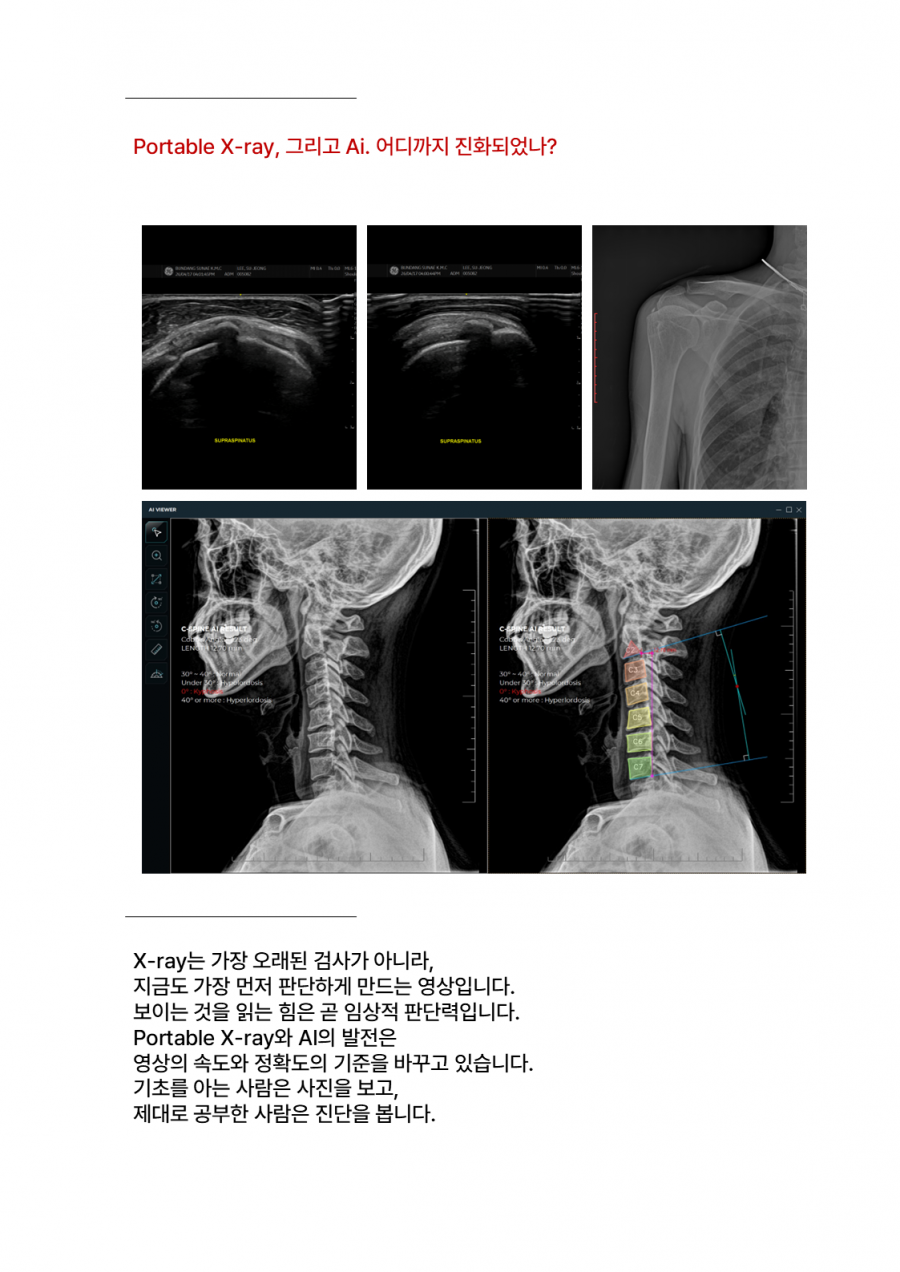

X-ray, All New 2026